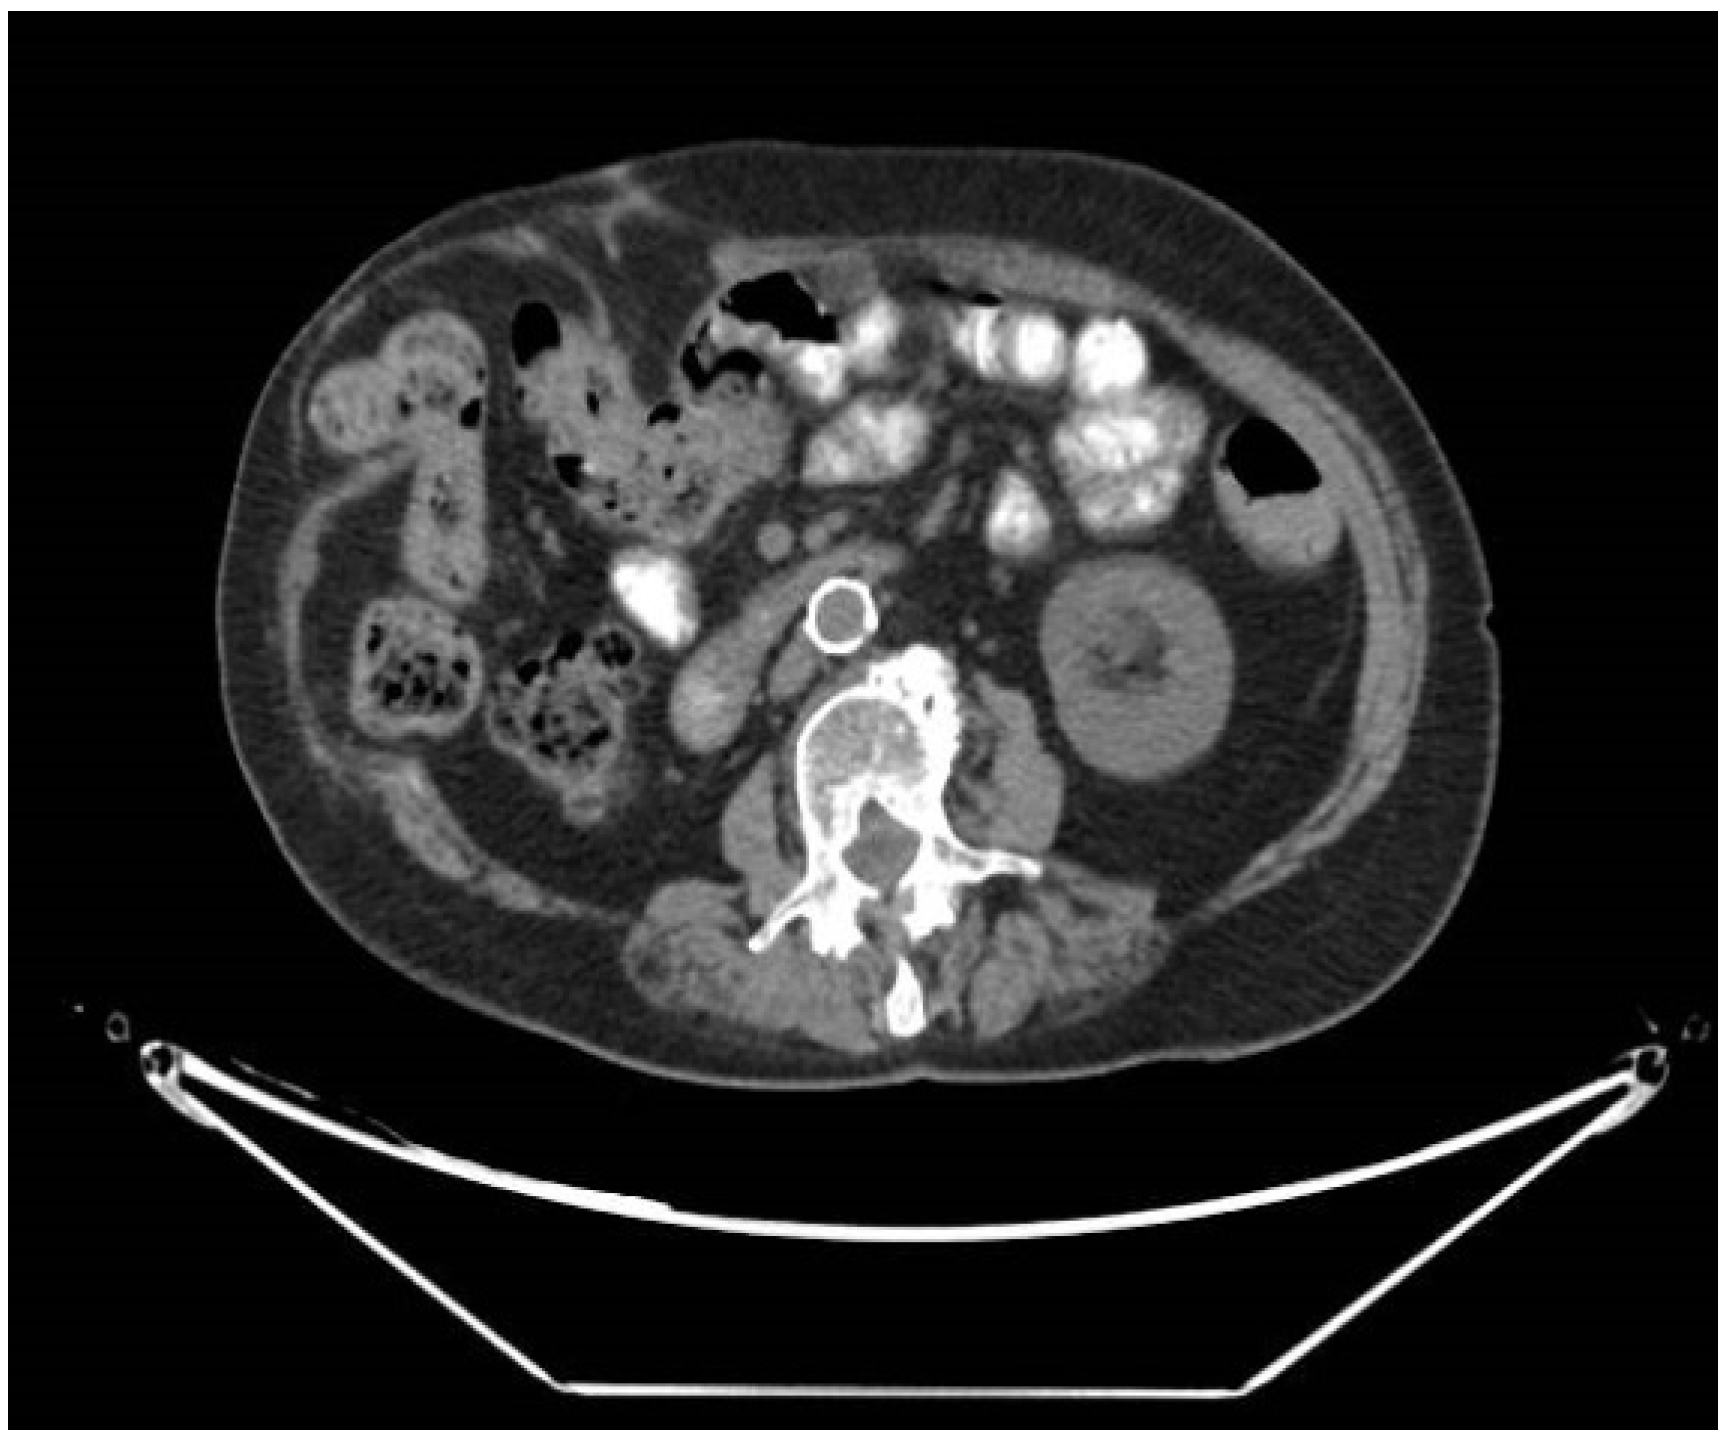

CT scans were retrospectively reviewed for all patients at least one year after surgery. A radiologist, blinded to the original radiological report and clinical results, reviewed all scans for abdominal wall herniation. This was correlated with documented clinical findings. Postoperative incisional hernia was radiologically defined as a disruption in the fascia at the site of the surgery (Figure 1).

CT scan with incisional hernia in the right abdominal horizontal incision.